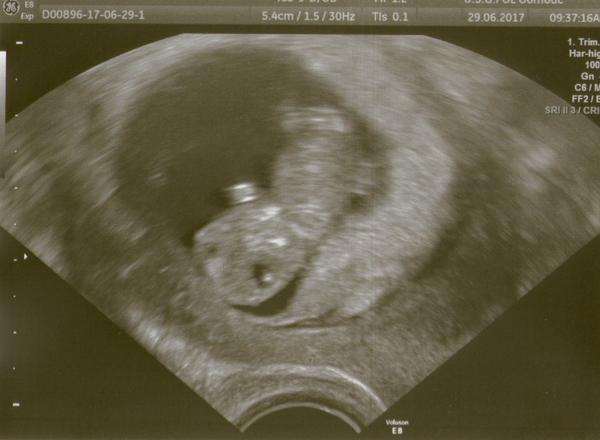

Já teď čekám na další kontrolu, ta už bude větší, 10.7., vůbec to neutika a vubec se necitim těhotně, nic mi není

Držím moc pěsti. Mě čeká kontrola taky 10.7.